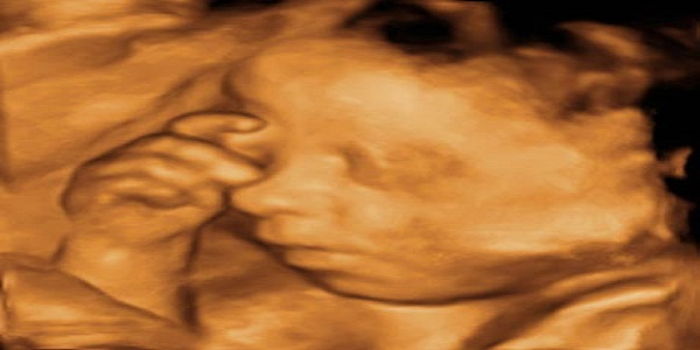

Detaylı ultrason taraması bebeğin neredeyse tüm organlarının tek tek incelendiği ve yaklaşık 30 45 dakika süren bir işlemdir. Bu inceleme yaklaşık olarak 20 30 dakika sürmektedir. Bebeğin boyu 15 17 cm aralığında olur. 20 hafta detaylı ultrason görüntüleri sonucunda bebek hakkında bazı bulgular elde edilir.

Ayrıntılı ultrasonografide önemli olan ultrason cihazının 3 veya 4 boyutlu olması değildir hatta 3 4 boyutlu olmasa da olur. Ayrıntılı taramada ilk olarak bebeğin 9 ay boyunca içinde gelişeceği ana rahmi inceleniyor ve ana rahmini besleyen damarlarda kan ölçümü yapılıyor. Gebelikte detaylı ultrason nasıl yapılır. Hafta itibariyle detaylı usg detaylı ultrason yada dört boyutlu tarama adlarıyla bu ultrason görüntüleme işlemi çıkar.

Detaylı ultrason hamilelik döneminde anne karnındaki bebeğin sağlık durumu ile ilgili son derece önemli veriler elde etmeyi sağlayan bir görüntüleme tetkikidir ultrasonografi cihazı kullanılarak gerçekleştirilen bu işlem sayesinde gebelik oldukça detaylı bir şekilde incelenebiliyor. Bunlardan bazılarını 2 haftalık gebelik ultrason görüntüleri 2 haftalık gebe karnı ve ilk hamilelik belirtileri şeklinde dile getirebileceğimiz gibi. Hamilelikte detaylı ultrason gebelik sürecinde rutin kontrollerde yapılan ultrason görüntülemesinden çok daha farklı bir işlemdir perinatoloji uzmanları tarafından yapılan bu görüntüleme tekniği anne karnındaki bebeğin anatomik açıdan detaylı bir şekilde incelenmesi amacıyla gerçekleştiriliyor. Bebeğin kilosu 280 310 gram aralığında olur.